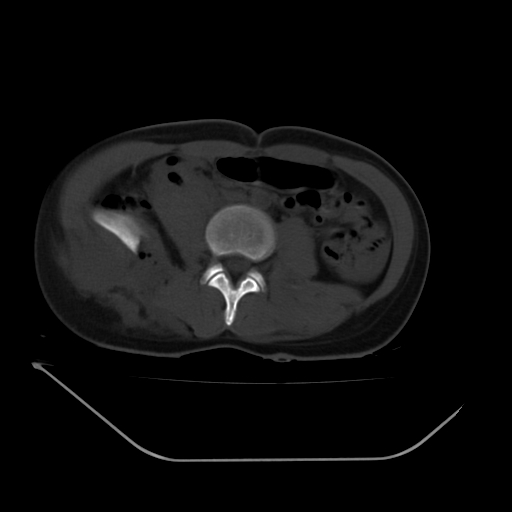

以下是引用liuyue在2008-7-19 13:02:00的发言:[br]1.肝右叶后下段及右肾挫裂伤伴腹腔积血。[br]2.右侧多发性肋骨骨折、横突骨折、右髂骨骨折伴周围软组织挫伤。[br]3.右侧腰大肌肿胀,并可见低密度影,如为气体,则肠道挫裂伤待除外。

以下是引用zhengfaming在2008-7-19 14:42:00的发言:[br]1.肝右叶后下段及右肾挫裂伤伴腹腔积血。脾脏挫裂伤待排[br]2.右侧多发性肋骨骨折、横突骨折、右髂骨骨折伴周围软组织挫伤。[br]3.右侧腰大肌肿胀,并可见低密度影,如为气体,则肠道挫裂伤待除外

以下是引用道哥在2008-7-19 16:52:00的发言:[br]肝右叶后下段及右肾挫裂伤、脾破裂伴腹腔积血。[br]2.双侧多发性肋骨骨折、横突骨折、右髂骨骨折伴周围软组织挫伤。[br]3.右侧腰大肌肿胀,并可见低密度影,如为气体,则肠道挫裂伤待除外。